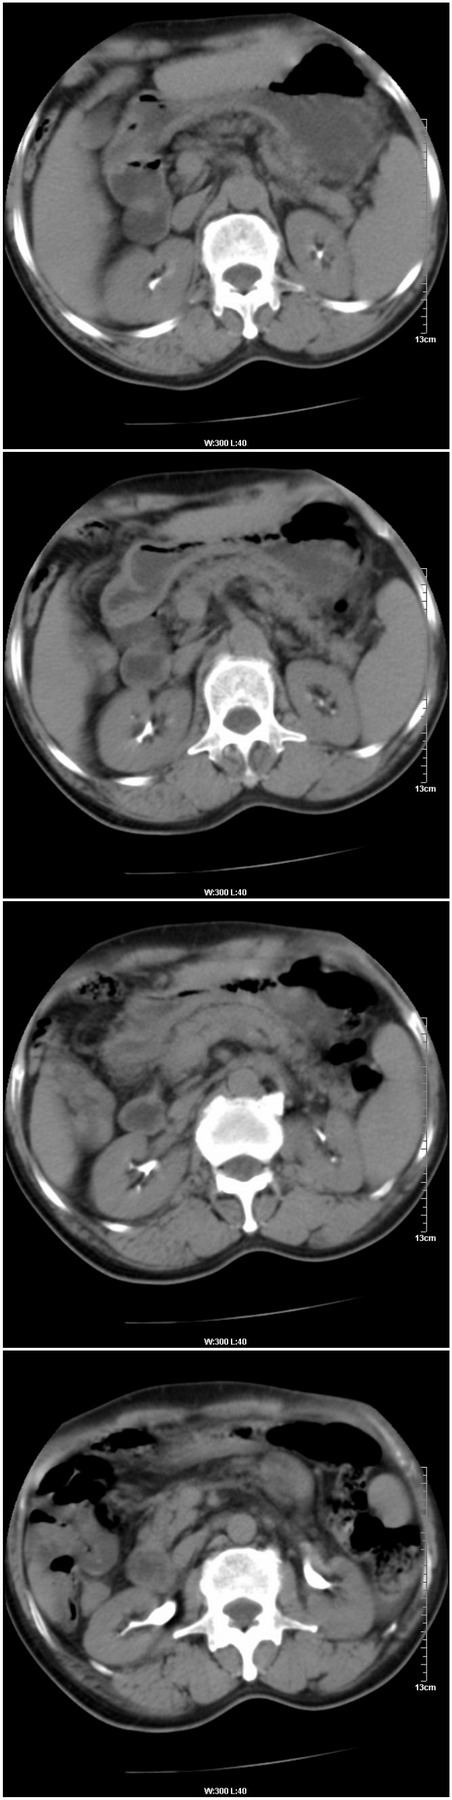

标题: [肝脏占位]CT13576:男性,57岁。胸腹痛伴消瘦半年余。 [打印本页]

标题: [肝脏占位]CT13576:男性,57岁。胸腹痛伴消瘦半年余。

增强情况:

病灶密度变化 正常肝组织密度变化

平扫病灶平均ct值:51.3hu 56hu

动脉期: 74.2hu 69hu

门脉期: 85.9hu 102 hu

4分钟后: 71.8hu 76hu

9分钟后: 71.9hu 72.9hu

这是又一例门脉期强化比动脉期强化明显的病例。往常我们所见到的都是由于肝癌是动脉供血,所以病变常在动脉期明显强化,而在门脉期就会下降。但是这一例和过去做过的一个病例都是在门脉期更明显强化,请战友们分析这种变化的实质。有人提出这是正常肝组织逐渐向肝癌转化的一个过程,也有人说这是另一种肝癌的类型,就是相对于一动脉供血为主的肝癌来说,这是一种以门脉供血为主的一种肝癌类型。战友们说说看,你认为怎样解释这种情况更合适呢?

1.肝右叶巨块性病变,周围有假包膜,内部密度不均,有坏死,增强后以门脉期强化明显,反应以门脉供血的特征,为不典型肝癌(梁索性)。

2.双肾及输尿管结石。

1.肝右叶巨块性病变,周围有假包膜,内部密度不均,有坏死,增强后以门脉期强化明显,反应以门脉供血为主的特征,为不典型肝癌(梁索性)。